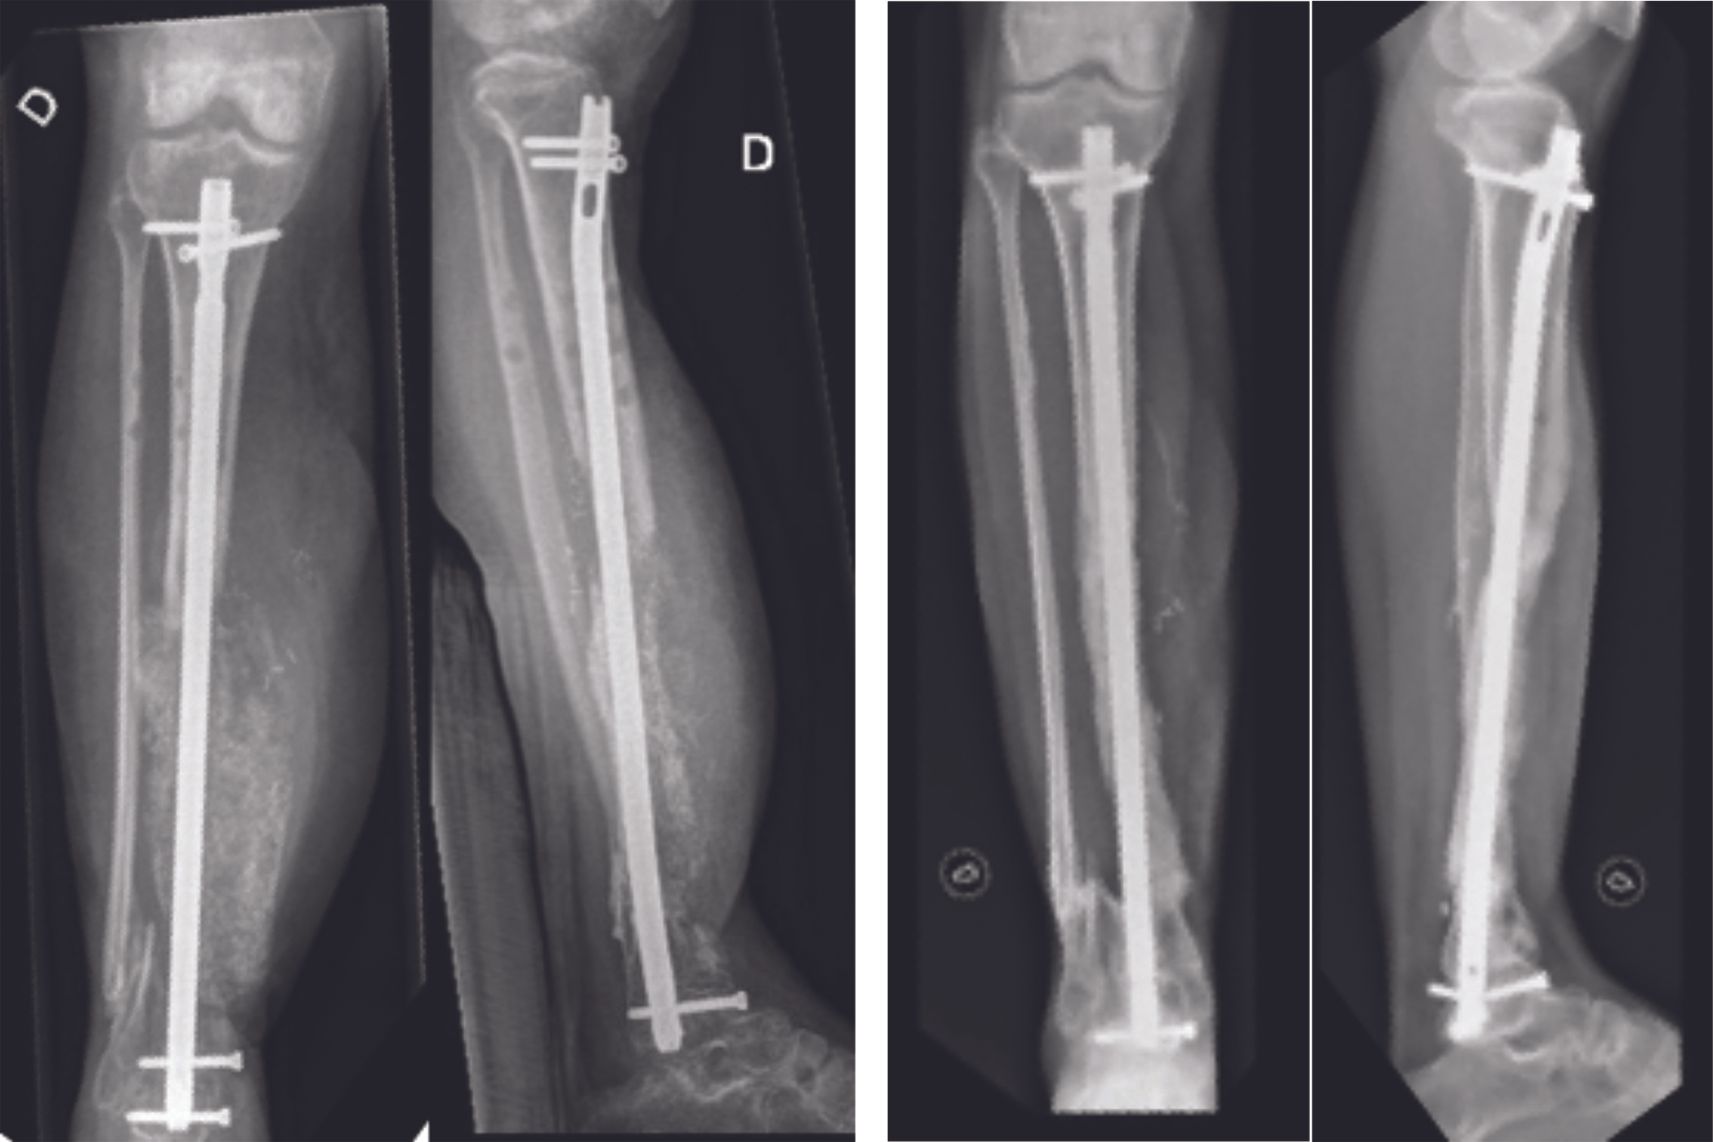

The second surgical stage includes removal of the cement spacer, bony reconstruction by bone grafting and final osteosynthesis (Fig. 4 and 5). The spacer is replaced by bone grafts harvested using the RIA (reamer – irrigator – aspirator) technique. The RIA technique allows large amounts of quality bone graft to be harvested if necessary. The induced membrane of the Masquelet technique avoids resorption of the bone graft and allows secondary bone healing.

The therapeutic strategy is to perform a resection of the pseudarthrosis until healthy bone is encountered (Fig. 6 A), insert an antibiotic bone cement spacer (Fig. 6 B) and then combine these local antibiotics with intravenous antibiotic therapy. In a second stage, which should be performed at least 6 weeks later, the surgeon replaces the spacer with a bone graft using the Masquelet technique or an intercalary prosthesis (Fig. 6 C). Intravenous antibiotic therapy should continue for several weeks post-surgery, depending on the type of infection.